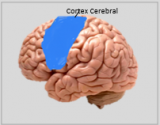

La neuroanatomie est la branche de l'anatomie qui étudie l'anatomie du système nerveux, c'est-à-dire la structure, la fonction et l'organisation du système nerveux.

Le système nerveux est l'un des systèmes les plus complexes du corps humain, et il comprend le cerveau, la moelle épinière, les nerfs périphériques et les ganglions nerveux. La neuroanatomie s'intéresse à la manière dont ces structures sont reliées les unes aux autres, comment les signaux sont transmis entre les cellules nerveuses, et comment les différentes parties du système nerveux travaillent ensemble pour contrôler les fonctions corporelles et cognitives. Les neuroanatomistes utilisent des techniques d'imagerie avancées, comme l'imagerie par résonance magnétique (IRM), la tomographie par émission de positons (TEP) et la microscopie pour visualiser les structures et les fonctions du système nerveux.